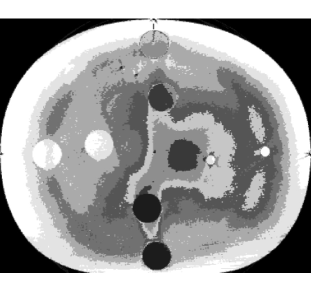

The cone-beam CT scans were acquired using a Varian linear accelerator with On-Board Imager (OBI) according to the same clinical protocol that is used for scanning prostate cancer patients. A half bow-tie filter was used to achieve a 450mm field of view. The dimensions of the reconstructed voxels were . The images were cropped using external image processing software (Schneider et al., 2012) to conform to the dimensions of the phantom: pixels and slices, or approximately . Summary statistics (observed mean and standard deviation) for each cone-beam CT scan are summarised in the supplementary material accompanying the electronic version of this paper. An axial slice from one of the cone-beam CT scans is shown in Fig. 3b.

The external field prior was precomputed according to Eq. (5). This prior was centred on the geometry of the ED phantom at 0 offset. We used a mean displacement of with standard deviation . This spatial variability corresponds to the prostate motion observed by Frank et al. (2008) in their study of 15 radiotherapy patients. The external field is illustrated in Fig. 3a.

The results are summarised in Table 2. Individual results for each cone-beam CT scan are available in the online supplementary material. An example of one of the segmentations is illustrated in Fig. 3d. When we estimated the effect size of the external field prior using paired differences, we found that it was dependent on the tissue type. For soft tissue (adipose, breast, liver and muscle) the 95% highest posterior density (HPD) interval for the paired differences in Dice coefficient (with and without the external field) was between 0.64 and 0.66. The smallest improvement was between 0.34 and 0.38 for lung (inhale). Overall, the mean voxel misclassification rate improved from 86.8% to 6.2%.